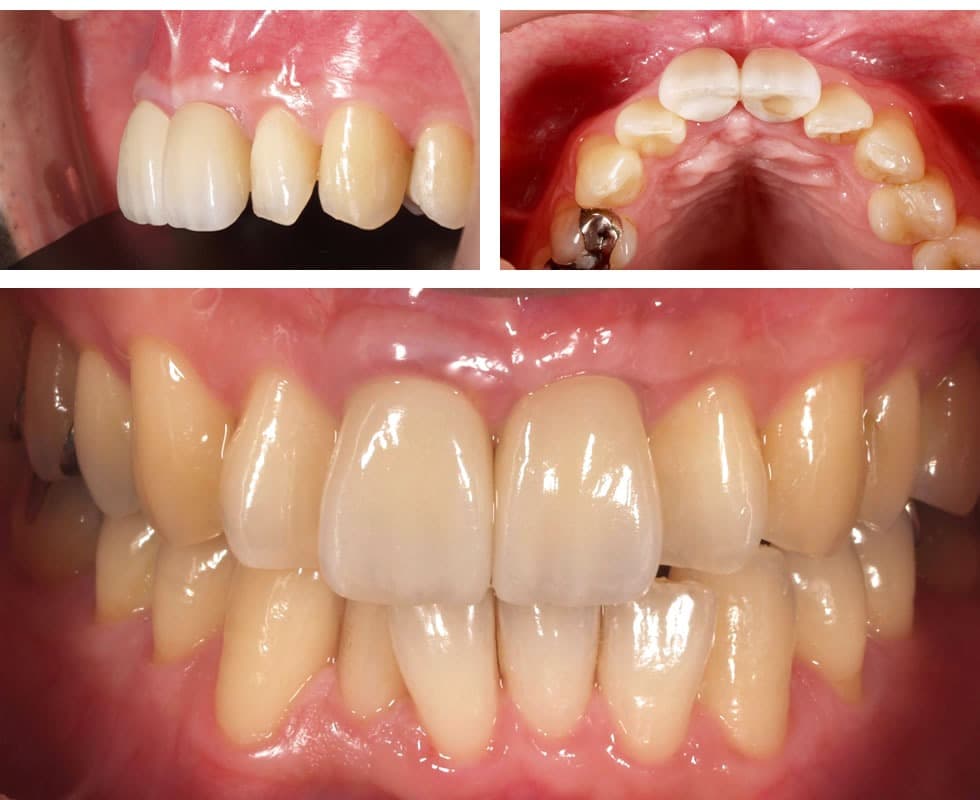

初診時

前歯を失った状態で時間が経過したため、骨が大きく吸収されています。

ファイナルレストレーション